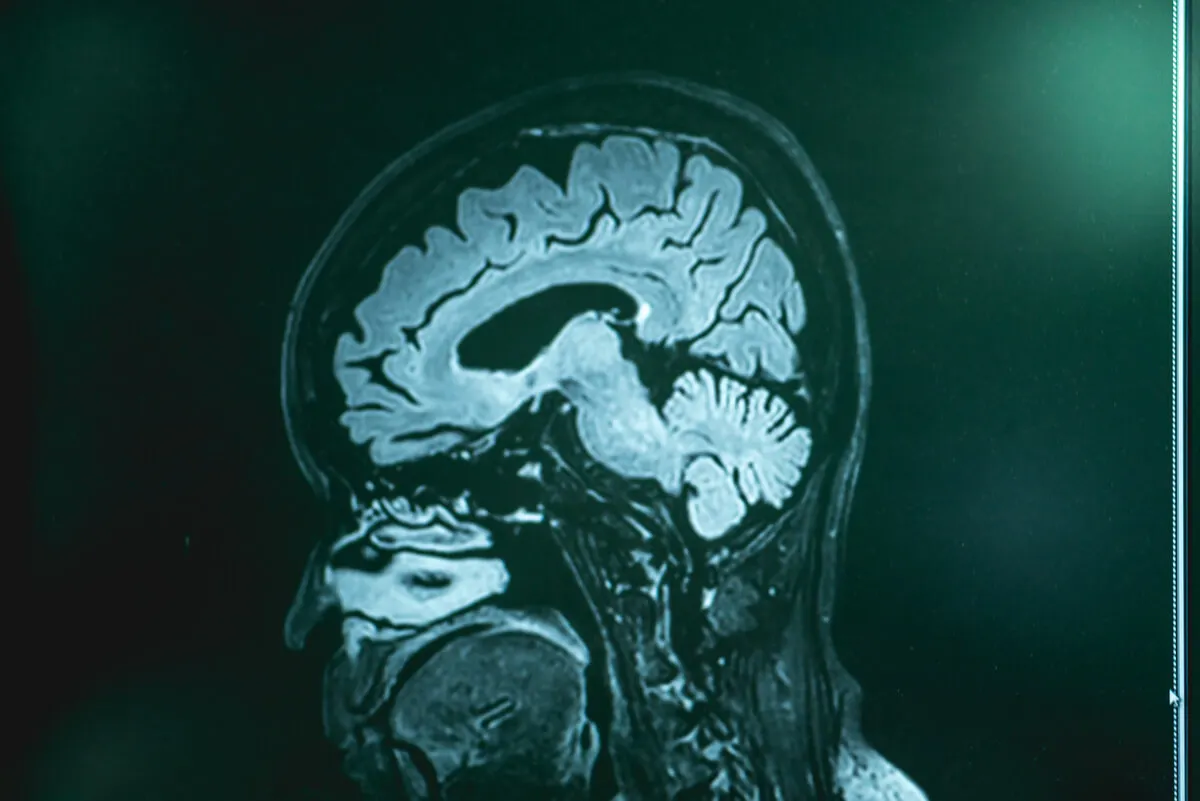

Jednym z najczęściej stosowanych jest rezonans magnetyczny. To badanie obrazowe umożliwia szczegółową obserwację tkanek mózgowych. Prawdopodobnie lekarz zleci również pełne badania krwi i płynu mózgowo-rdzeniowego. Aby pobrać płyn do badania, należy wykonać nakłucie lędźwiowe.